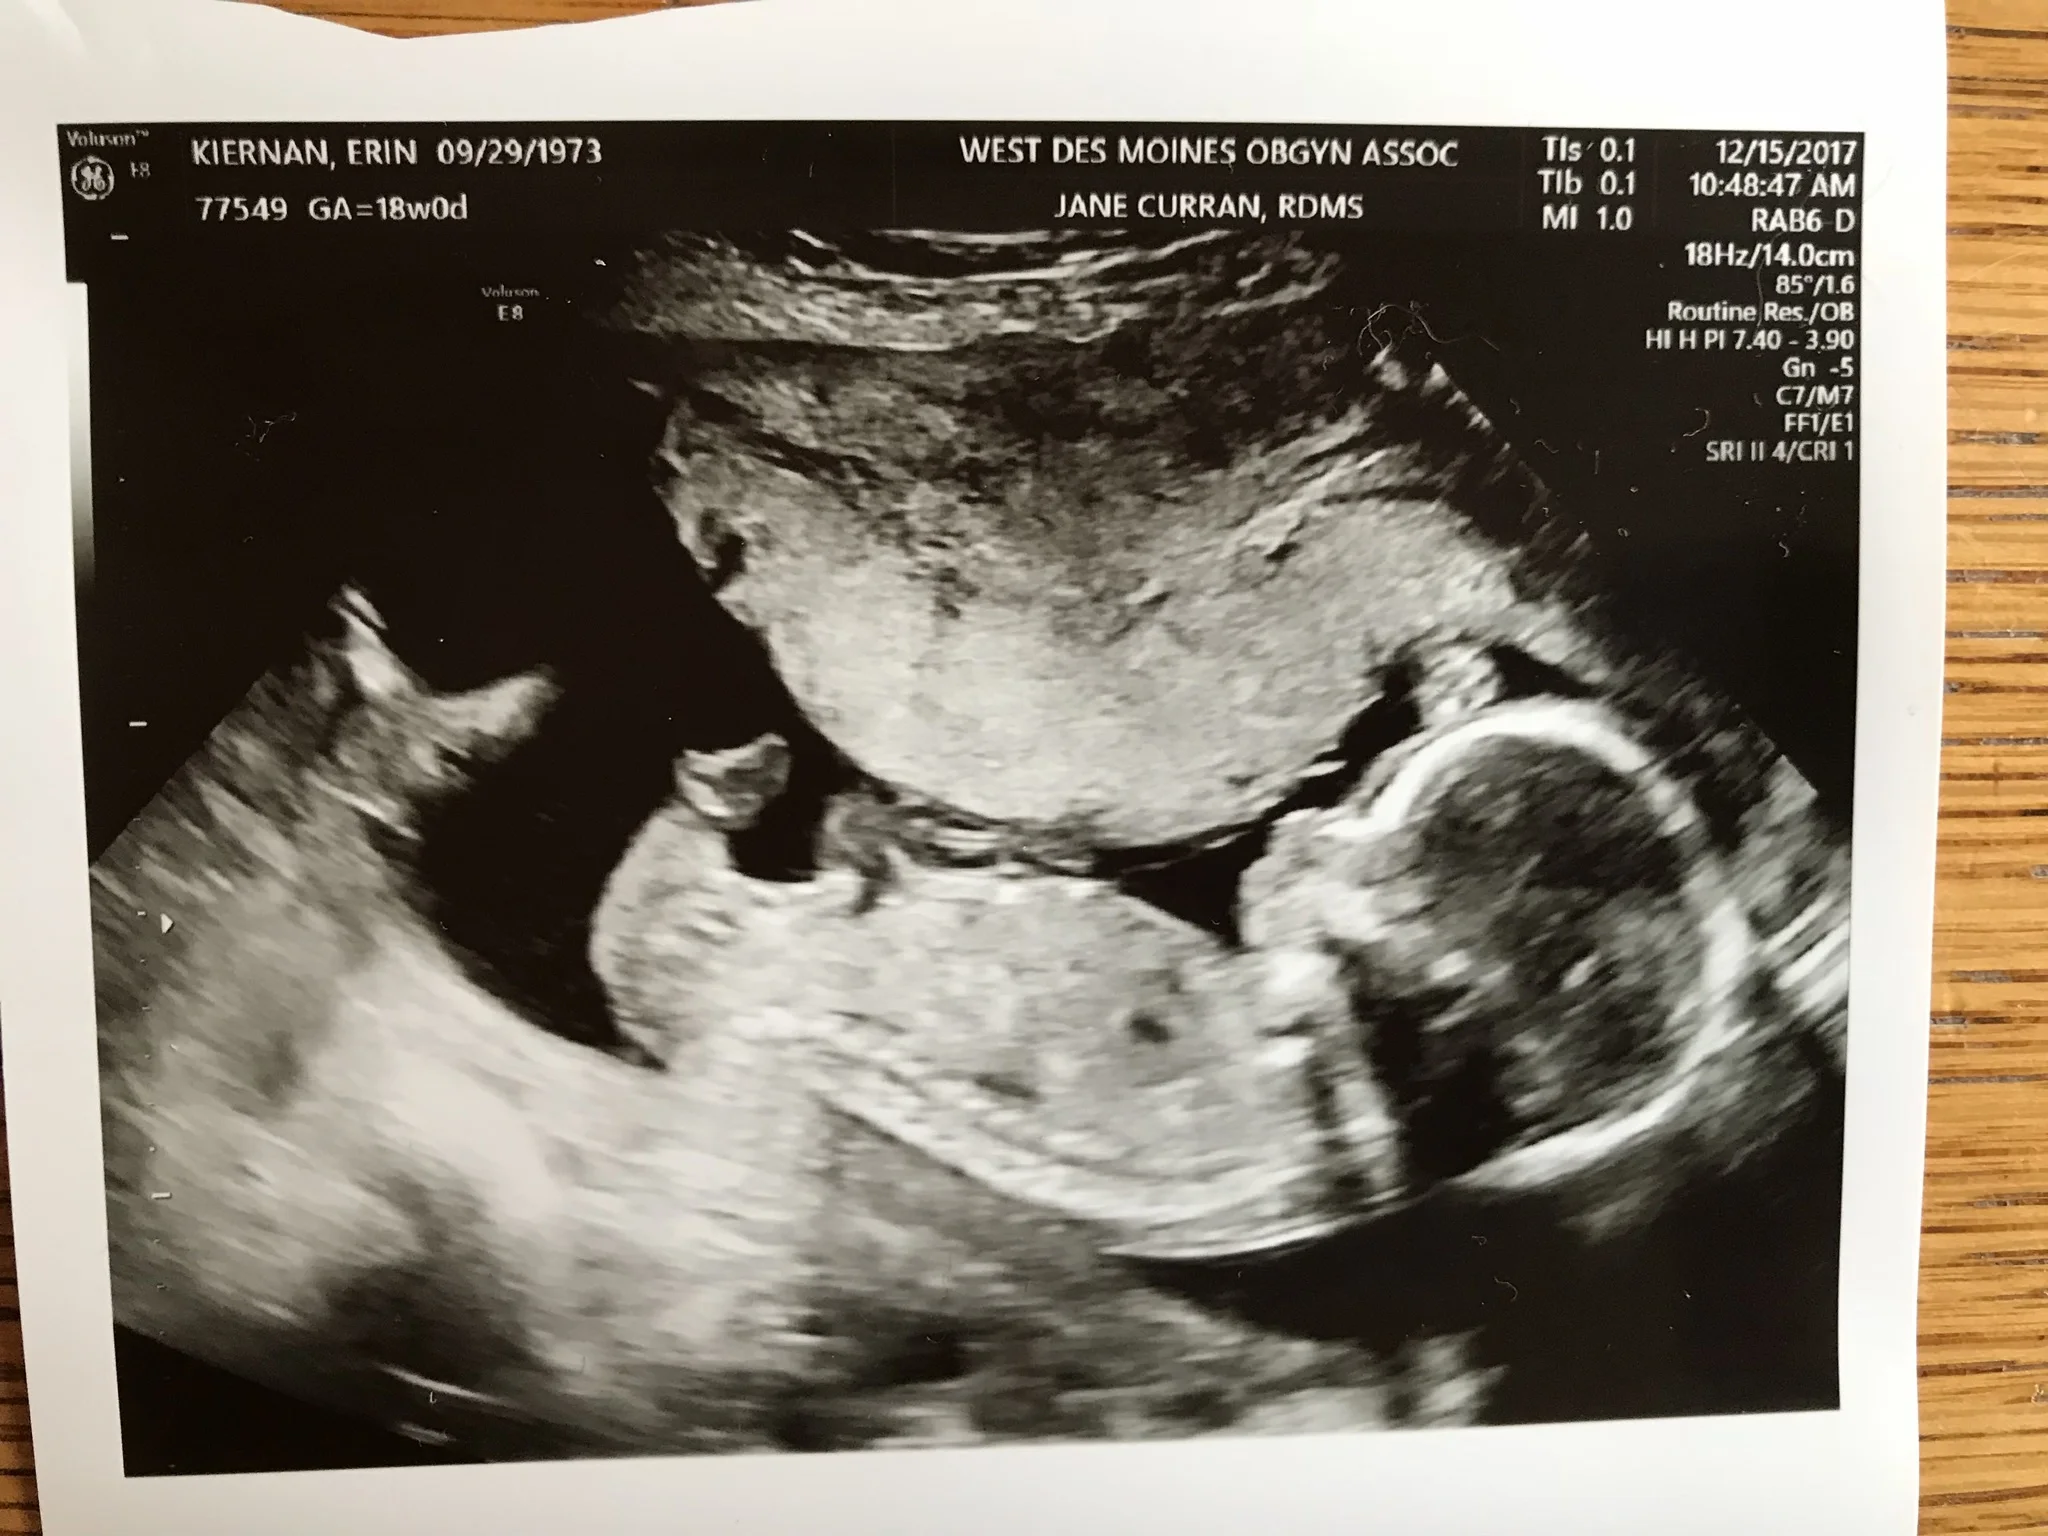

Overcoming Fear Infertility, Health & Fitness, FamilyErin KiernanDecember 15, 2017infertility, fear, anxiety, pregnancy, family